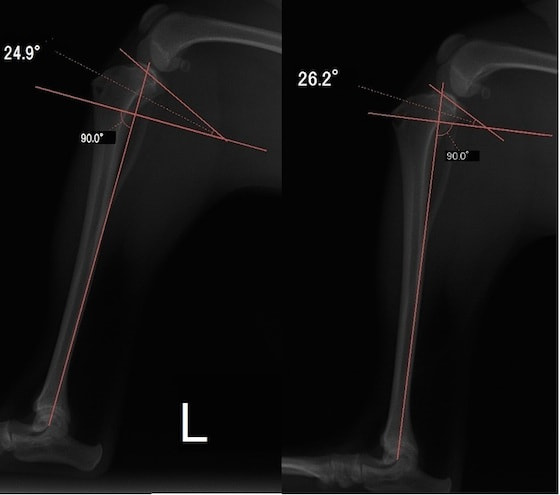

■ 症例22 ポメラニアン 1歳5か月 去勢雄

左後肢の挙上を主訴に来院した。整形学的検査、レントゲン検査より左右の膝蓋骨脱臼(左GradeⅡ〜Ⅲ、右Grade Ⅱ)を認めた。また、脛骨の前方引き出し試験の際に、引き出し兆候は認められないものの、疼痛が認められたため、前十字靭帯の損傷が疑われた。術中における、目視および関節内の操作によって、前十字靭帯の損傷や過伸展といった異常が認められなかったため、膝蓋骨脱臼の整復のみ実施した。手術手技は縫工筋及び内側広筋の解放、脛骨粗面の外側転位、滑車ブロック形造溝術、内外側関節包の縫縮を実施した。本症例は跛行もなく経過良好である。しかし、頸骨高平部の角度(TPA)が 右26.2°、左24.9°であり、解剖学的に前十字靭帯損傷のリスクが高いことから今後の経過に注意が必要である。